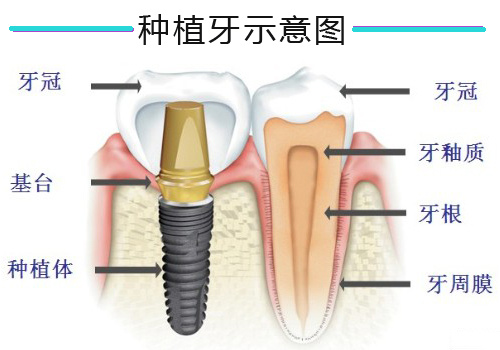

种植也可以称为“即拔即种”,种植技术简单来说,就是直接在拔牙后的位置上打一个小孔,在里面放入种植牙根,然后这颗牙根就能够跟牙槽骨进行紧密的结合。这种纯钛金属跟骨头之间的牢固结合就是种植牙的科学理论基础。